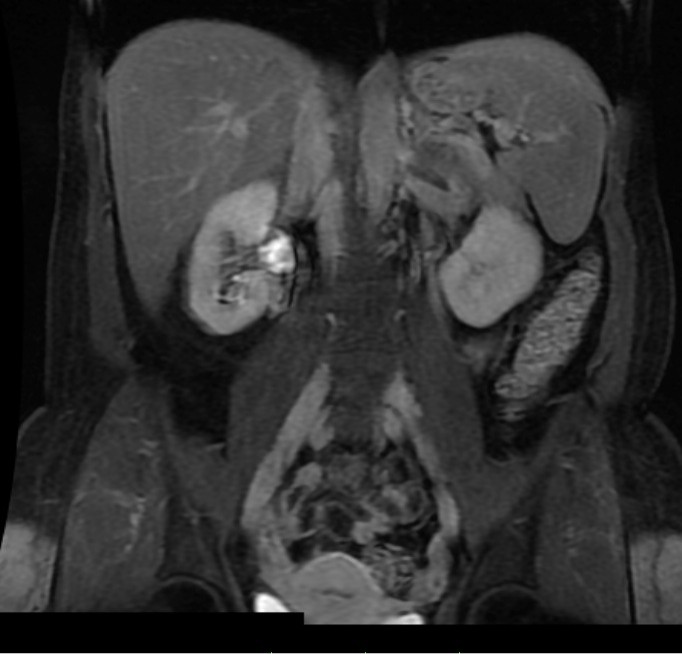

Hi Caryn, What you have posted is a single, coronal , early venous phase T1 weighted scan. You can see the liver, spleen and kidneys. The kidneys look white due to the contrast. Unfortunately, an MR scan produces data that could provide hundreds of images. These are taken in transverse, coronal and sagittal planes. They are also done in T1, T2 and Spinecho sequences. They are also done in noncontrast, arterial, saturation, venous and late venous phases. That is why an MR takes a while, and you would have had to 'hold your breath' for each sequence. MR scans are diagnosed on a computer with several high def. screens. Images are manipulated, 3D images are obtained, and by scrolling through the images of all of the sequences, a diagnosis is made. Sample images are often printed out for the benefit of the referring doctor. We used to give patients a CD with relevant films.

So essentially, diagnosing an MR is complex, requires lots of computing power and multiple image monitors. A single image means nothing. Sorry.

Alright, I hope this is a good shot. From the last test which was a fibroscan, I was told probably between stage 2-3 fibrosis. This is an MRI I had done today in preperation of upcoming treatment. I hope someone can comment. I wont hold you to it - I am going to see my specialist in a few weeks.